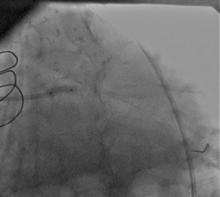

A 59 male patient - with known ESRD, CABG 5 years ago, and implantation of a 3.0x24mm Biomatrix frmo the LM to the LCX 6 months ago - was admitted with ongoing crushing chest pain 3 years ago. ECG showed diffuse ST depression in all precordial leads (figure 1). At initial presentation he developed VF and underwent mechanical ventilation.

1) LM: subtotal ISR lesion (figure 2, figure 3)